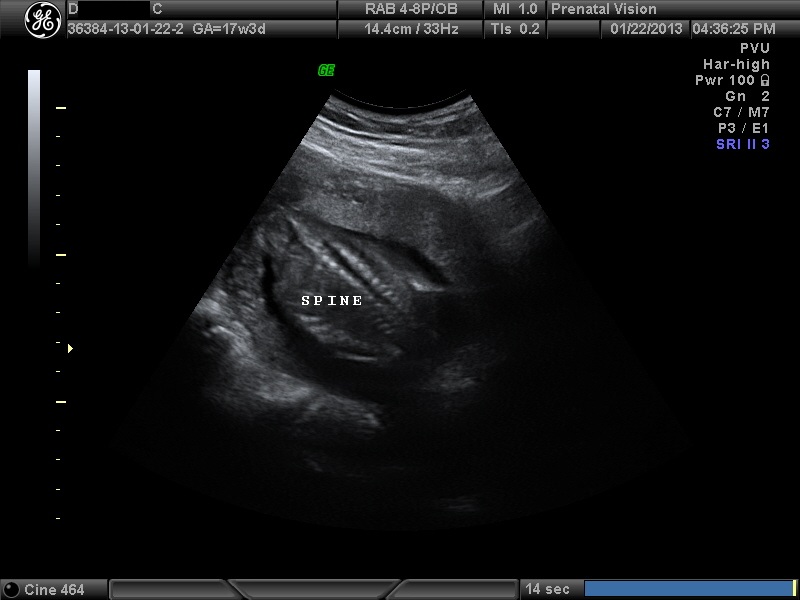

IMAGES_10 January 22, 2013 by Courtney Leave a comment ← Previous Image Next Image → 17w3d Like Loading...